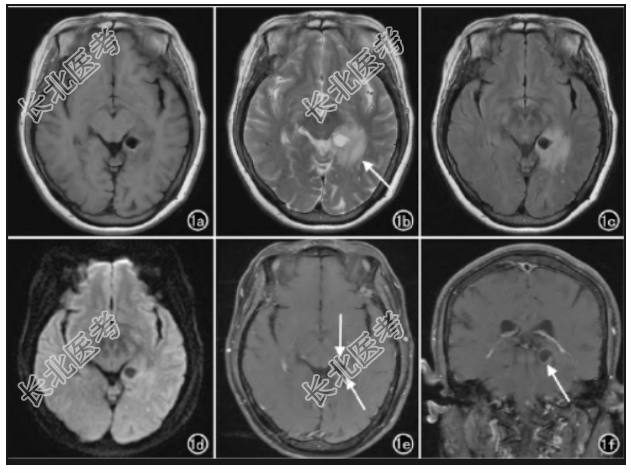

实验室检查:肌酸激酶同工酶GMB20U/L。影像学表现:MRI平扫左侧颞叶G海马区见不规则囊实性异常信号,边界欠清晰,大小约4.0cm×3.1cm,实性部分T1WI呈等、低混杂信号,T2WI、FLAIR呈高信号,DWI呈等、稍高信号;囊性部分大小约1.3cm×1.1cm,位于海马尾,信号欠均匀,T1WI、FLAIR、DWI呈中心低信号、边缘高信号,T2WI呈中心高信号、边缘低信号(图1a~1d)。增强扫描绕囊性病变周围斑片状轻度强化,其余未见强化(图1e、1f)。初步诊断为左侧颞叶G海马区低级别神经元胶质瘤。镜下示肿瘤细胞由大的神经节细胞及明显多样性的胶质细胞组成(图1g)。初步诊断为左侧颞叶节细胞胶质瘤。

说明:1a:T1WI轴面示病变实性部分呈等、低混杂信号,囊性部分呈中心低信号、边缘高信号;1b:T2WI示病变实性部分呈高信号,囊性部分呈中心高信号、边缘低信号(箭);1c:FLAIR示病变实性部分呈高信号,囊性部分呈中心低信号、边缘高信号;1d:DWI示病变囊性部分呈中心低信号、边缘高信号,实性部分呈等、稍高信号;1e:MRI增强扫描轴面示绕囊性病变周围斑片状强化(箭),其余未见强化;1f:MRI增强扫描冠状面示绕囊性病变周围斑片状强化(箭),其余未见强化;1g:镜下示肿瘤细胞由大的神经节细胞及明显多样性的胶质细胞组成(×200,HE)。